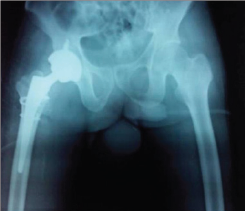

Under general anesthesia, the patient was positioned laterally and a Moore's posterior approach was taken guided by dislocation and wall fracture. The gluteus maximus had a huge rent and external rotators were torn, the head was seen indenting the sciatic nerve (bowstring effect) which was contused but intact (Figure 3a). The neck was ostetomised with help of saw at the appropriate level and the calcar was reconstructed using encirclage wiring (Figure 3b). Ethibond was used to suture the greater trochanter. Next 2 temporary K wires were used in the ace tabular walls and reaming done and cement less cup size 52 was fixed augmented with 2 screws (Figure 3c). The K wires were removed after the cup was found stable. The femur was prepared and uncemeneted corail stem size 11 was inserted and size 36x0 femoral head was found stable. C arm was used to confirm the placement of implants (Figure 3d). All soft tissues were closed in best possible way, the hip was stable (Figure 3e). An abductor brace was applied post operatively. Postoperatively day one faradic stimulation was started and patient was allowed side tuning. Check X ray was done which showed a reasonable reconstruction (Figure 4). The patient was allowed sitting with non weight bearing mobilization from day 3 after the pain had subsided. 3 weeks after surgery the patient was discharged when he went back to his home state and never came back for follow up.

Figure 4.